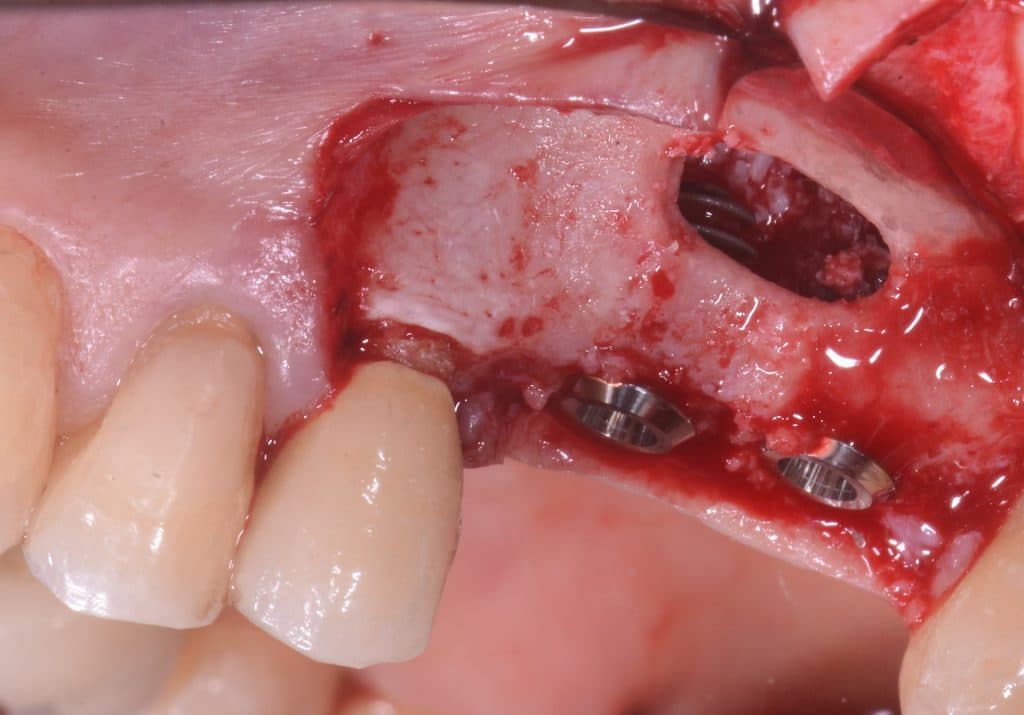

- Lateral wall window – Tool: sonic 2 mm ball bur (by Komet)

- CBCT helps us for the exact position of the window

- Be careful do not perforate the Schneider’s membrane with bur

- 2mm micro periosteal elevator (by Meta) to remove the residual bone and reveal the cleavage plane

- Two implants are placed drilling the 3 mm of residual crestal bone

- You can see the apexes of the depth indicators inside the maxillary sinus

- Implants can be seen inside the maxillary sinus through the bone window